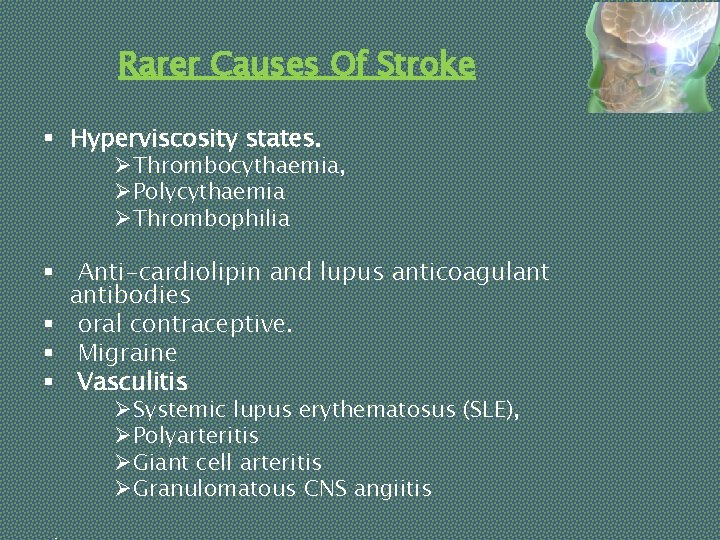

Rarer Causes Of Stroke § Hyperviscosity states. ØThrombocythaemia, ØPolycythaemia ØThrombophilia § Anti-cardiolipin and lupus anticoagulant antibodies § oral contraceptive. § Migraine § Vasculitis ØSystemic lupus erythematosus (SLE), ØPolyarteritis ØGiant cell arteritis ØGranulomatous CNS angiitis

Rarer Causes Of Stroke § § § Amyloidosis. Hyperhomocysteinaemia Neurosyphilis Mitochondrial disease Drugs Ø Sympathomimetic drugs Ø cocaine Ø Vasoconstrictors Ø neuroleptics • CADASIL (cerebral dominant arteriopathy with subcortical infarcts and leucoencephalopathy)